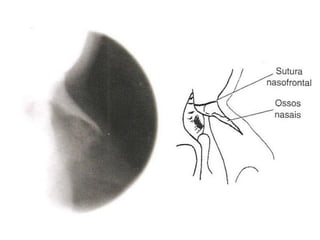

Radiografia do crânio

• Estruturas internas são mais estudadas com aquisições de

imagens mais detalhadas.

Alterações visualizadas:

Fraturas;

Neoplasias;

Inflamações;

Distúrbios articulares (ATM);

Lesões por PAF;

Adenomas hipofisários;

Mieloma múltiplo;

Doença de Paget (osteíte deformante).

Ossos nasais